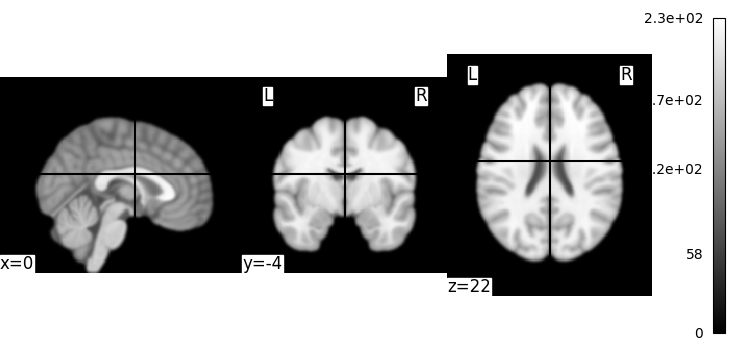

Let’s use an image-smoothing function from nilearn:

smooth_img

Functions containing ‘img’ can take either a filename or an image as input.

Here we give as inputs the image filename and the smoothing value in mm

from nilearn import image

smooth_anat_img = image.smooth_img(MNI152_FILE_PATH, fwhm=3)

This is an in-memory object. We can pass it to nilearn function, for instance to look at it

<nilearn.plotting.displays._slicers.OrthoSlicer object at 0x7f1ee8e6fac0>